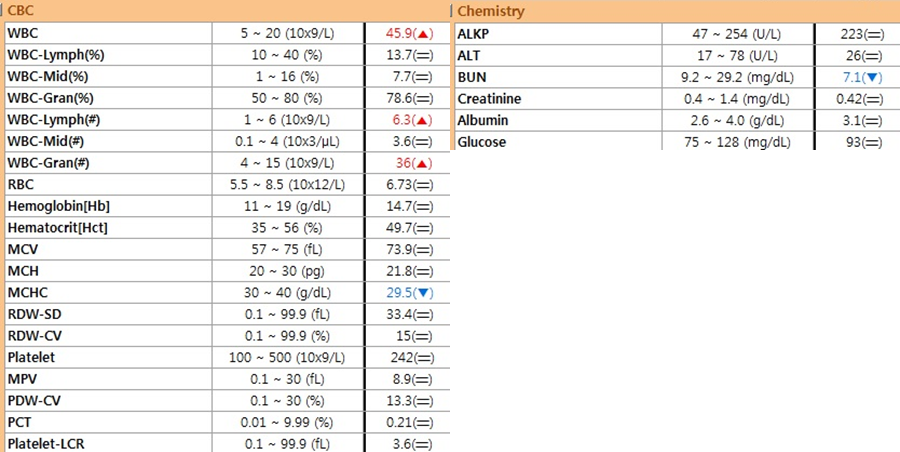

▶ 혈액 검사 마취 전의 컨디션을 확인하기 위해 혈액 검사와 흉부 방사선 검사를 실시했습니다.

수술요크셔테리어 강아지 자궁축농증수술 I 부평프라임동물병원 마취전 혈액검사상 염증수치가 많이 상승하였음을 확인 할 수 있습니다충분한 수액 처치를 통한 탈수 교정 후 호흡 마취를 안전하게 유도하고 수술을 시행하였습니다.